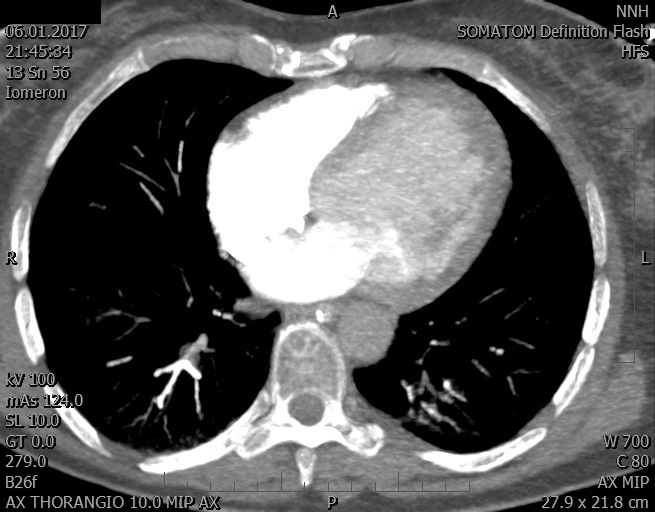

Video 1 - Akutní koronarografie prokázala normální nález na věnčitých tepnách s výjimkou suspekce na lehký spasmus na pravé koronární tepně.Echokardiograficky byla zjištěna těžká dysfunkce dilatované levé komory s nezvětšenou pravou komorou (video 2).

Video 2 - Echokardiograficky byla zjištěna těžká dysfunkce dilatační levé komory s nezvětšenou pravou komorou.Pro nejasnou příčinu zástavy jsme provedli i vyšetření výpočetní tomografií (CT), které vyloučilo plicní embolizaci (série 1 - soubory na konci článku). V den přijetí při přetrvávající oběhové nestabilitě byla nemocná opakovaně defibrilována pro fibrilaci komor se stabilizací rytmu po podání amiodaronu a mesocainu. Dle hemodynamických měření se jednalo o těžký kombinovaný šok. Vstupní laboratorní vyšetření bylo bez větších pozoruhodností. Posléze jsme doplnili anamnézu od příbuzných a zjistili, že pacientka užila do dvou hodin před srdeční zástavou první tabletu amoxicilinu na lehký respirační infekt. Při nevýtěžnosti vstupních vyšetření a nových anamnestických informacích jsme doplnili 14 hodin po kolapsu vyšetření koncentrace tryptázy v séru, která byla extrémně zvýšena (tabulka 2), což nás vedlo k podezření na anafylaxi.